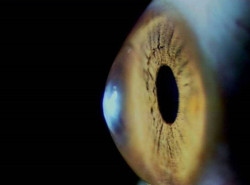

Los científicos dan un paso importante hacia el uso de trasplantes de células de retina para tratar la ceguera

Células de la retina derivadas de un ojo humano de cadáver sobrevivieron cuando se trasplantaron a ojos de modelos de primates, un avance importante en el desarrollo de la terapia celular para tratar la ceguera, según un estudio publicado en la revista `Stem Cell Reports`.